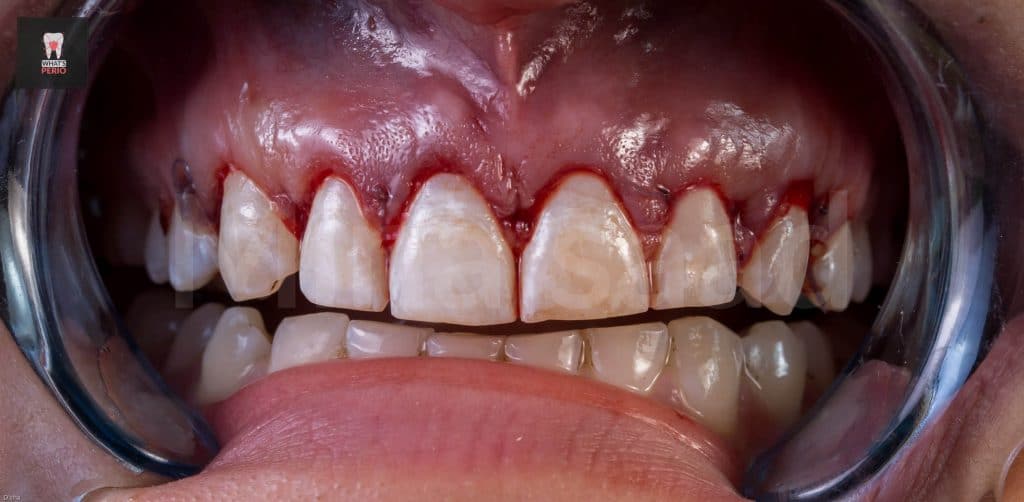

-External bevel gingivectomy was made while the guide in place.

-Internal bevel incision was made “envelope flap” to expose underlying labial plate of bone.

-Ostectomy was made using a rose head diamond stone then the guide was put in place again & it was observed that the apical level & the alveolar crest is at the same level now.

-Osteoplasty wass performed to reshape the prominent canine eminence to be in harmony with the left one & in general the labial plate of bone was shaped & any sharp angles resulting from ostectomy procedure were removed for better adaptation of the flap ensuring nice healing results.

-The flap was sutured using single sling sutures. “4/0 Vicryl sutures” “resorbable”